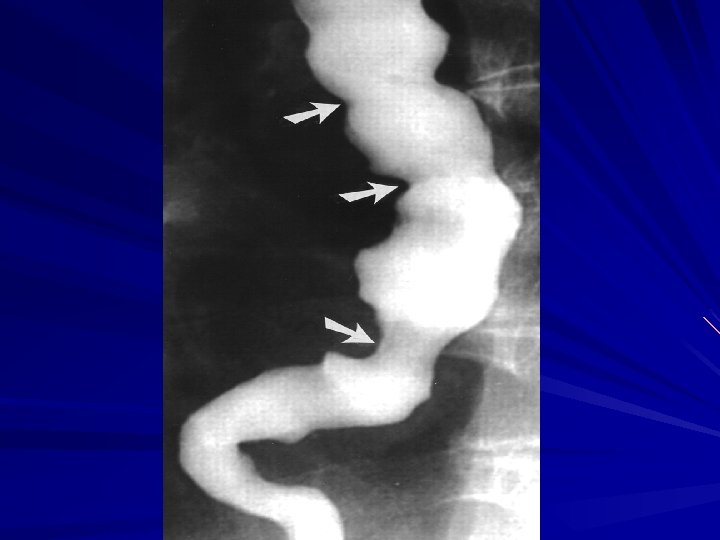

Diffuse Esophageal Spasm DES is a hypermotility disorder of the esophagus is seen most often in women and is often found in patients with multiple complaints The basic pathology is related to a motor abnormality of the esophageal body that is most notable in the lower two thirds of the esophagus

Diffuse Esophageal Spasm the esophageal contractions are repetitive, simultaneous, and of high amplitude

Symptoms and Diagnosis irritable bowel syndrome and pyloric spasm, may accompany DES, whereas other gastrointestinal problems, such as gallstones, peptic ulcer disease, and pancreatitis, all trigger DES The diagnosis of DES is made by an esophagram and manometric studies

Esophagram A barium esophagram is recommended for any patient presenting with dysphagia is able to differentiate intraluminal from intramural lesions and to discriminate between intrinsic (from a mass protruding into the lumen) and extrinsic (from compression of a structures outside the esophagus) compression

Esophagram The classic finding of an apple-core lesion in patients with esophageal cancer is recognized easily Although the esophagram will not be specific for cancer, it is a good first test to perform in patients presenting with dysphagia and a suspicion of esophageal cancer